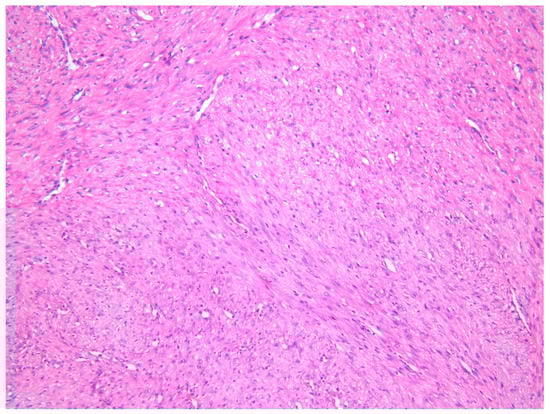

The lesion was excised under general anesthesia using an intraoral approach, with the specimen consisting of two soft tissues masses together measuring 3.0 × 2.5 × 1.5 cm in size with soft and hard tissue removed from buccal and posterior margins, respectively. The hematoxylin and eosin-stained section revealed an un-encapsulated tumor composed of spindle cells arranged into long fascicles (Figure 1). The tumor cells showed vesicular nuclei and eosinophilic cytoplasms. The cells exhibited a mild degree of cytological atypia with moderately high mitotic counts (8 per 10 HPF). In contrast, Ki-67 activity was 5 per 100 cells (Figure 2). Stag horn-like hemangiopericytomatous vasculature was evident throughout the lesion. These histopathological findings together with the immunohistochemical findings of smooth muscle actin (SMA) (Figure 3) and vimentin positivity (Table 1) were consistent with the diagnosis of low-grade myofibroblastic sarcoma. As the surgical margins were positive for tumor, re-excision was performed to obtain clear margins. The patient remained free of disease 12 months after the re-excision.

Figure 1. Photomicrograph exhibiting low-grade myofibroblastic sarcoma (LGMS) composed of spindle-shaped cells arranged into fascicles—Case 1 (hematoxylin and eosin stain ×10).